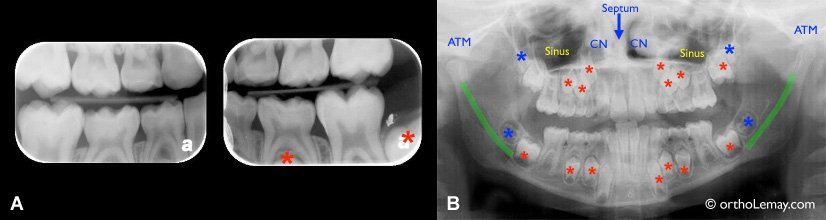

L’identification des lésions proximales est classiquement effectuée à l’aide de clichés rétrocoronaires. Cependant, ils présentent le désavantage de sous-estimer la profondeur des lésions et nécessitent, pour une bonne interprétation des lésions et de leur progression, d’être renouvelés à différentes dates et dans les mêmes conditions de prise des clichés.